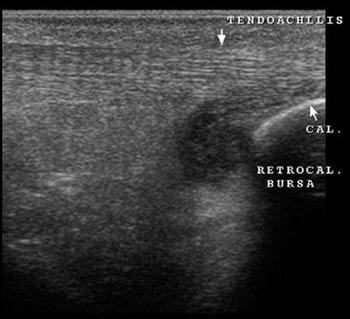

Retrocalcaneal bursitis: hypoechoic collection is seen near the site of insertion of the tendo-achillis on calcaneum.